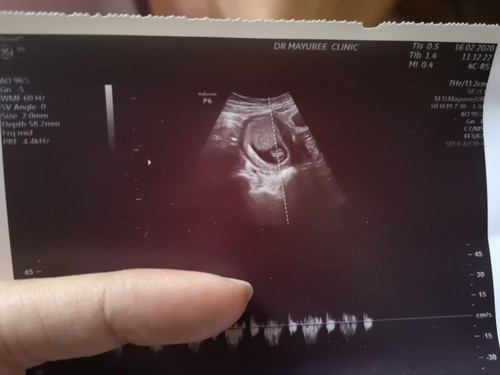

ในภาพเปนการวัดการเต้นของหัวใจน้องค่ะ นี่คือวิธีอ่านใบซาวด์ค่ะ